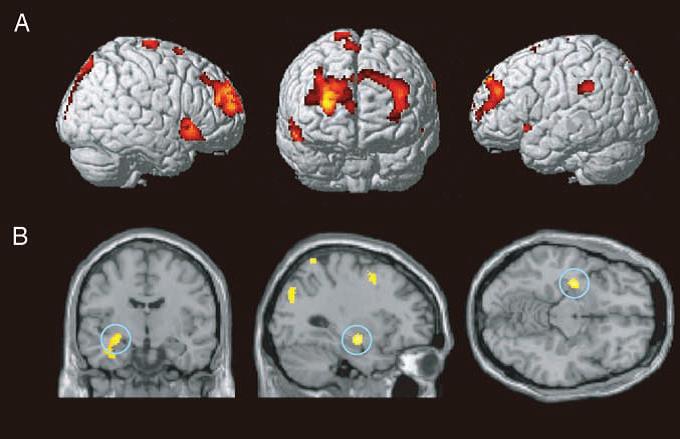

Короткочасна пам’ять

Короткочасна (робоча) пам’ять має обмежений обсяг і здатна утримуватися протягом декількох хвилин завдяки механізмам «уявного повторення». Її формування відбувається в корі лобових часток. Відомості, що містяться в короткочасній пам’яті, здатні перероблятися, структуруватися і перетворюватися в довготривалу пам’ять. Цей процес називається консолідацією сліду пам’яті, який займає від кількох годин до доби.

Довготривала (декларативна) пам’ять може вміщати безмежну кількість інформації, яка здатна зберігатися все життя. Цей вид пам’яті утримує смислове (подієву) складову отриманих відомостей. Вона поділяється на:

Детальна етіологія амнезії і її різновидів все ще не встановлена. Імовірно органічні ушкодження полягають в повній дисфункції ряду церебральних нейронів і розриві їх межнейрональних зв’язків в лімбічної системі, яка реєструє, кодує, а потім відтворює наявну інформацію.